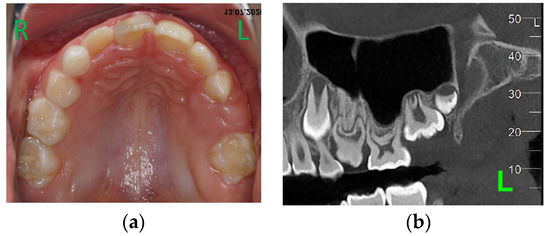

At the age of 12 y and 11 m, while the upper canines were erupting, the clinical and radiological situation in the distal part of the upper left quadrant was not much different from before (Figure 8a–c).

Figure 8.

Age of 12 y and 11 m. Intraoral pictures (a,b) and panoramic X-rays (c) showed retained 26 and 27.